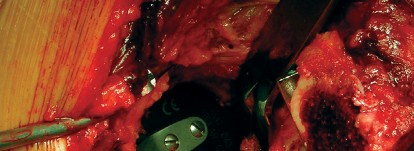

الخلاصة الطبية الشاملة: يُعتبر طول عمر مكون الحُق الأسمنتي في مفصل الورك الصناعي حجر الزاوية لنجاح جراحة استبدال مفصل الورك الكلي. يعتمد هذا النجاح بشكل كبير على التخطيط الدقيق قبل الجراحة، والتغطية الكافية من عظم المريض السليم، والتثبيت الأمثل للمكون بتقنيات أسمنتية حديثة. تتضمن الجراحة تقييمًا معمقًا لجودة العظم، إزالة دقيقة للنتوءات العظمية، وتطبيق مادة الأسمنت الطبي الحيوي لضمان تثبيت قوي ومستقر للحُق، مما يكفل الاستقرار والديمومة طويلة الأمد للمفصل الصناعي. مع المتابعة الدورية والالتزام بالبرنامج التأهيلي، يمكن للمرضى التمتع بنتائج ممتازة ونوعية حياة محسنة لسنوات عديدة. في صنعاء، يبرز الأستاذ الدكتور محمد هطيف كخبير رائد في هذا المجال، حيث يجمع بين الخبرة العميقة والتقنيات المتطورة لتقديم أفضل رعاية جراحية.

في جراحة استبدال مفصل الورك الكلي، يتم استبدال رأس عظم الفخذ التالف بمكون معدني كروي، ويتم استبدال الحُق الطبيعي المتضرر بمكون حُقي صناعي. المكون الحُقي الأسمنتي هو عبارة عن كوب معدني أو بلاستيكي عالي الجودة (عادة من البولي إيثيلين) يتم تثبيته داخل تجويف الحُق في عظم الحوض باستخدام "الأسمنت العظمي" (Bone Cement)، وهو مادة بوليمرية حيوية تعمل كغراء قوي لتثبيت المكون بشكل فوري ومستقر.